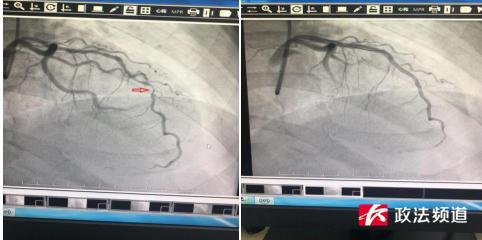

冠状动脉造影显示 , 奚先生的冠状动脉前降支已经堵塞了近95% , 几乎就剩下一条线了 。 随后 , 王勇为奚先生置入了3枚支架 , 闭塞的血管被成功开通 , 牙痛的症状也随即消失了 。

(图为奚先生支架手术术前、术后对比 , 箭头处为前降支血管约有95%的狭窄)